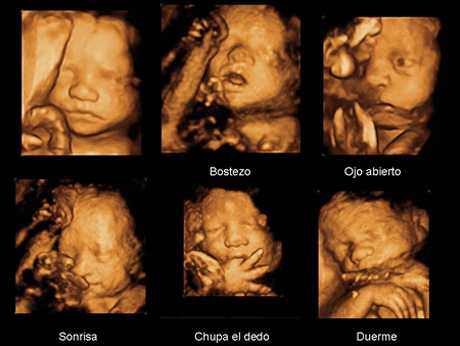

En los últimos tiempos las ecografías han ido evolucionando como toda la tecnología y nos encontramos con imágenes en 3 dimensiones (3D y 4D), estas ecografías cumplen la función de implementar la ecografía en dos dimensiones, en esta técnica se puede observar correctamente el volumen del niño, apreciar su rostro, sus gestos, las imágenes son nítidas y en color, y permiten al especialista ver los huesos y la piel del feto, y se utiliza para detectar patologías a nivel renal, cardíaco y pulmonar.

Por otro lado tenemos las ecografías en 4D, que son una ecografía 3D pero con movimiento, y permite ver los movimientos del bebé que pronto nacerá en tiempo real, hace mediciones casi exactas y precisas, y le permiten a los papás ver un vídeo de como su futuro hijo saca la lengua, mueve sus manitas, los pies, y navega dentro del vientre de su madre.

La verdad vale la pena realizar por lo menos una ecografía 3D/4D durante tu embarazo. Ya que podrás apreciar perfectamente la carita de tu bebé, incluso podrás verle, riéndose, tragando líquido amniótico e incluso chupándole su dedo pulgar. Toda una experiencia que no deben perderse los padres.